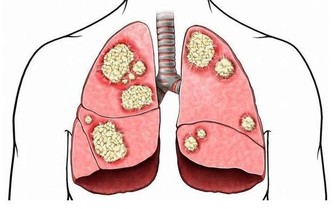

肺部是呼吸系統重要的器官,人們的輕鬆的呼吸、乾淨的血液都依靠肺部的運行。當肺部出現了健康問題,對於整個身體健康是有很大影響的,甚至會危及到生命,所以及時知曉肺部的求救信號是非常重要的。睡覺時有哪些異常情況是肺在求救呢?接下來讓我們一起來了解一下。

肺部受損是一件比較重大的事,出現了肺部疾病也不要拖延,一定要及早治療,這樣才能把後果盡量的降到最低。